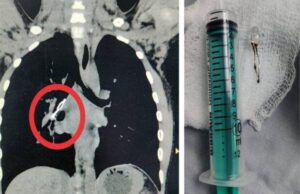

महबूबनगर का नौ साल का बच्चा प्रकाश दोस्तों के साथ खेलते-खेलते अचानक एलईडी बल्ब निगल लिया। सांस लेने और खांसने में दिक्कत हुई तो उसने घर वालों को अपनी परेशानी बताई। सोमवार को घर वाले उसे डॉक्टर के पास ले गए तो उसकी तुरंत सीटी स्कैन कराई गई। सीटी स्कैन में उसके फेफड़े के अंदर वाली ट्यूब के निचले हिस्से में एक छोटा एलईडी बल्ब और तार दिखा। डॉक्टरों ने उसकी ब्रोंकोस्कोपी करके उसे दस मिनट में ही बिना किसी दिक्कत के बाहर निकाल दिया। बच्चा बिल्कुल स्वस्थ है। खास बात यह है कि बच्चे को उसी दिन अस्पताल से छुट्टी दे दी गई।

डॉक्टरों के अनुसार, आमतौर पर हम देखते हैं कि 4 या 5 वर्ष से कम उम्र के बच्चे खेल-खेल में कोई कड़ी चीज, बीज और खिलौने के छोटे-छोटे टुकड़े इत्यादि निगल जाते हैं। लेकिन इस मामले में यह अधिक खतरनाक था। इसमें एलईडी बल्ब के साथ नीचे की ओर धातु का एक छोटा तार लगा था। यह मुख्य वायुमार्ग को खराब कर सकता था। साथ ही इसकी वजह से रासायनिक प्रतिक्रियाओं के कारण या आंतरिक रक्तस्राव के कारण भी जटिलता आ सकती थी। जब यह और गहराई से अंदर चली जाती तो उसको निकालना और अधिक मुश्किल हो जाती। तब उसको निकालने के लिए खुली सर्जरी की जरूरत पड़ती। उन्होंने कहा कि बल्ब 12 घंटे से अधिक समय तक शरीर के अंदर था।